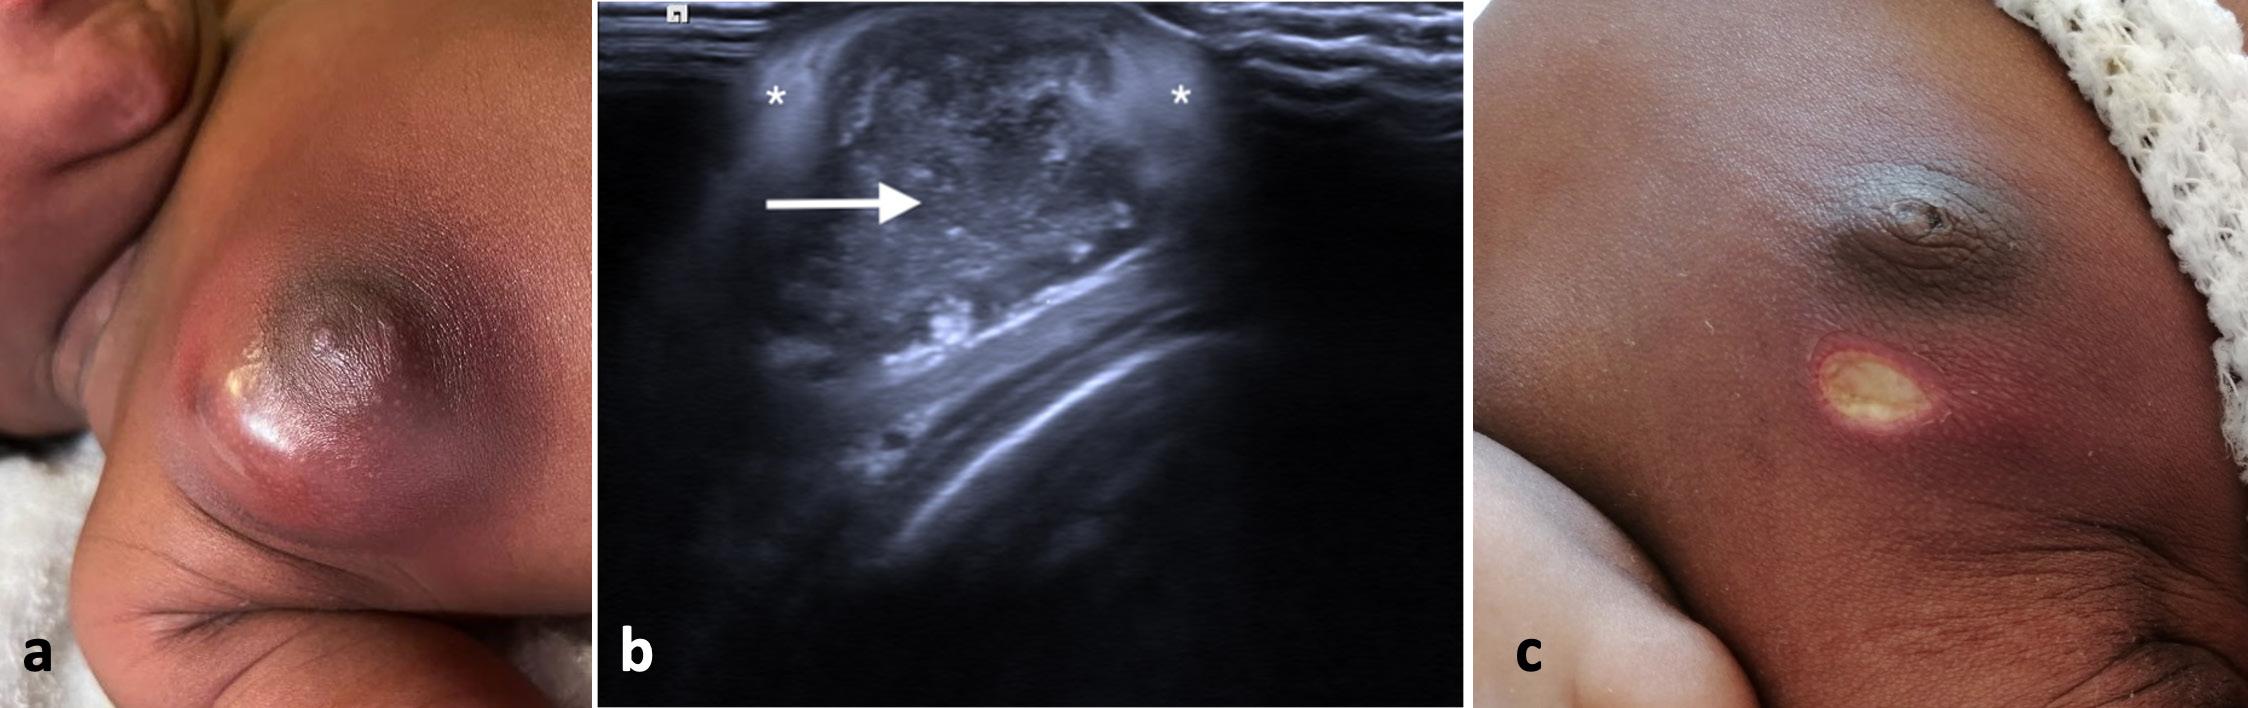

26 La mastite neonatale

Francesco Accomando, Melodie O. Aricò, Enrico Valletta